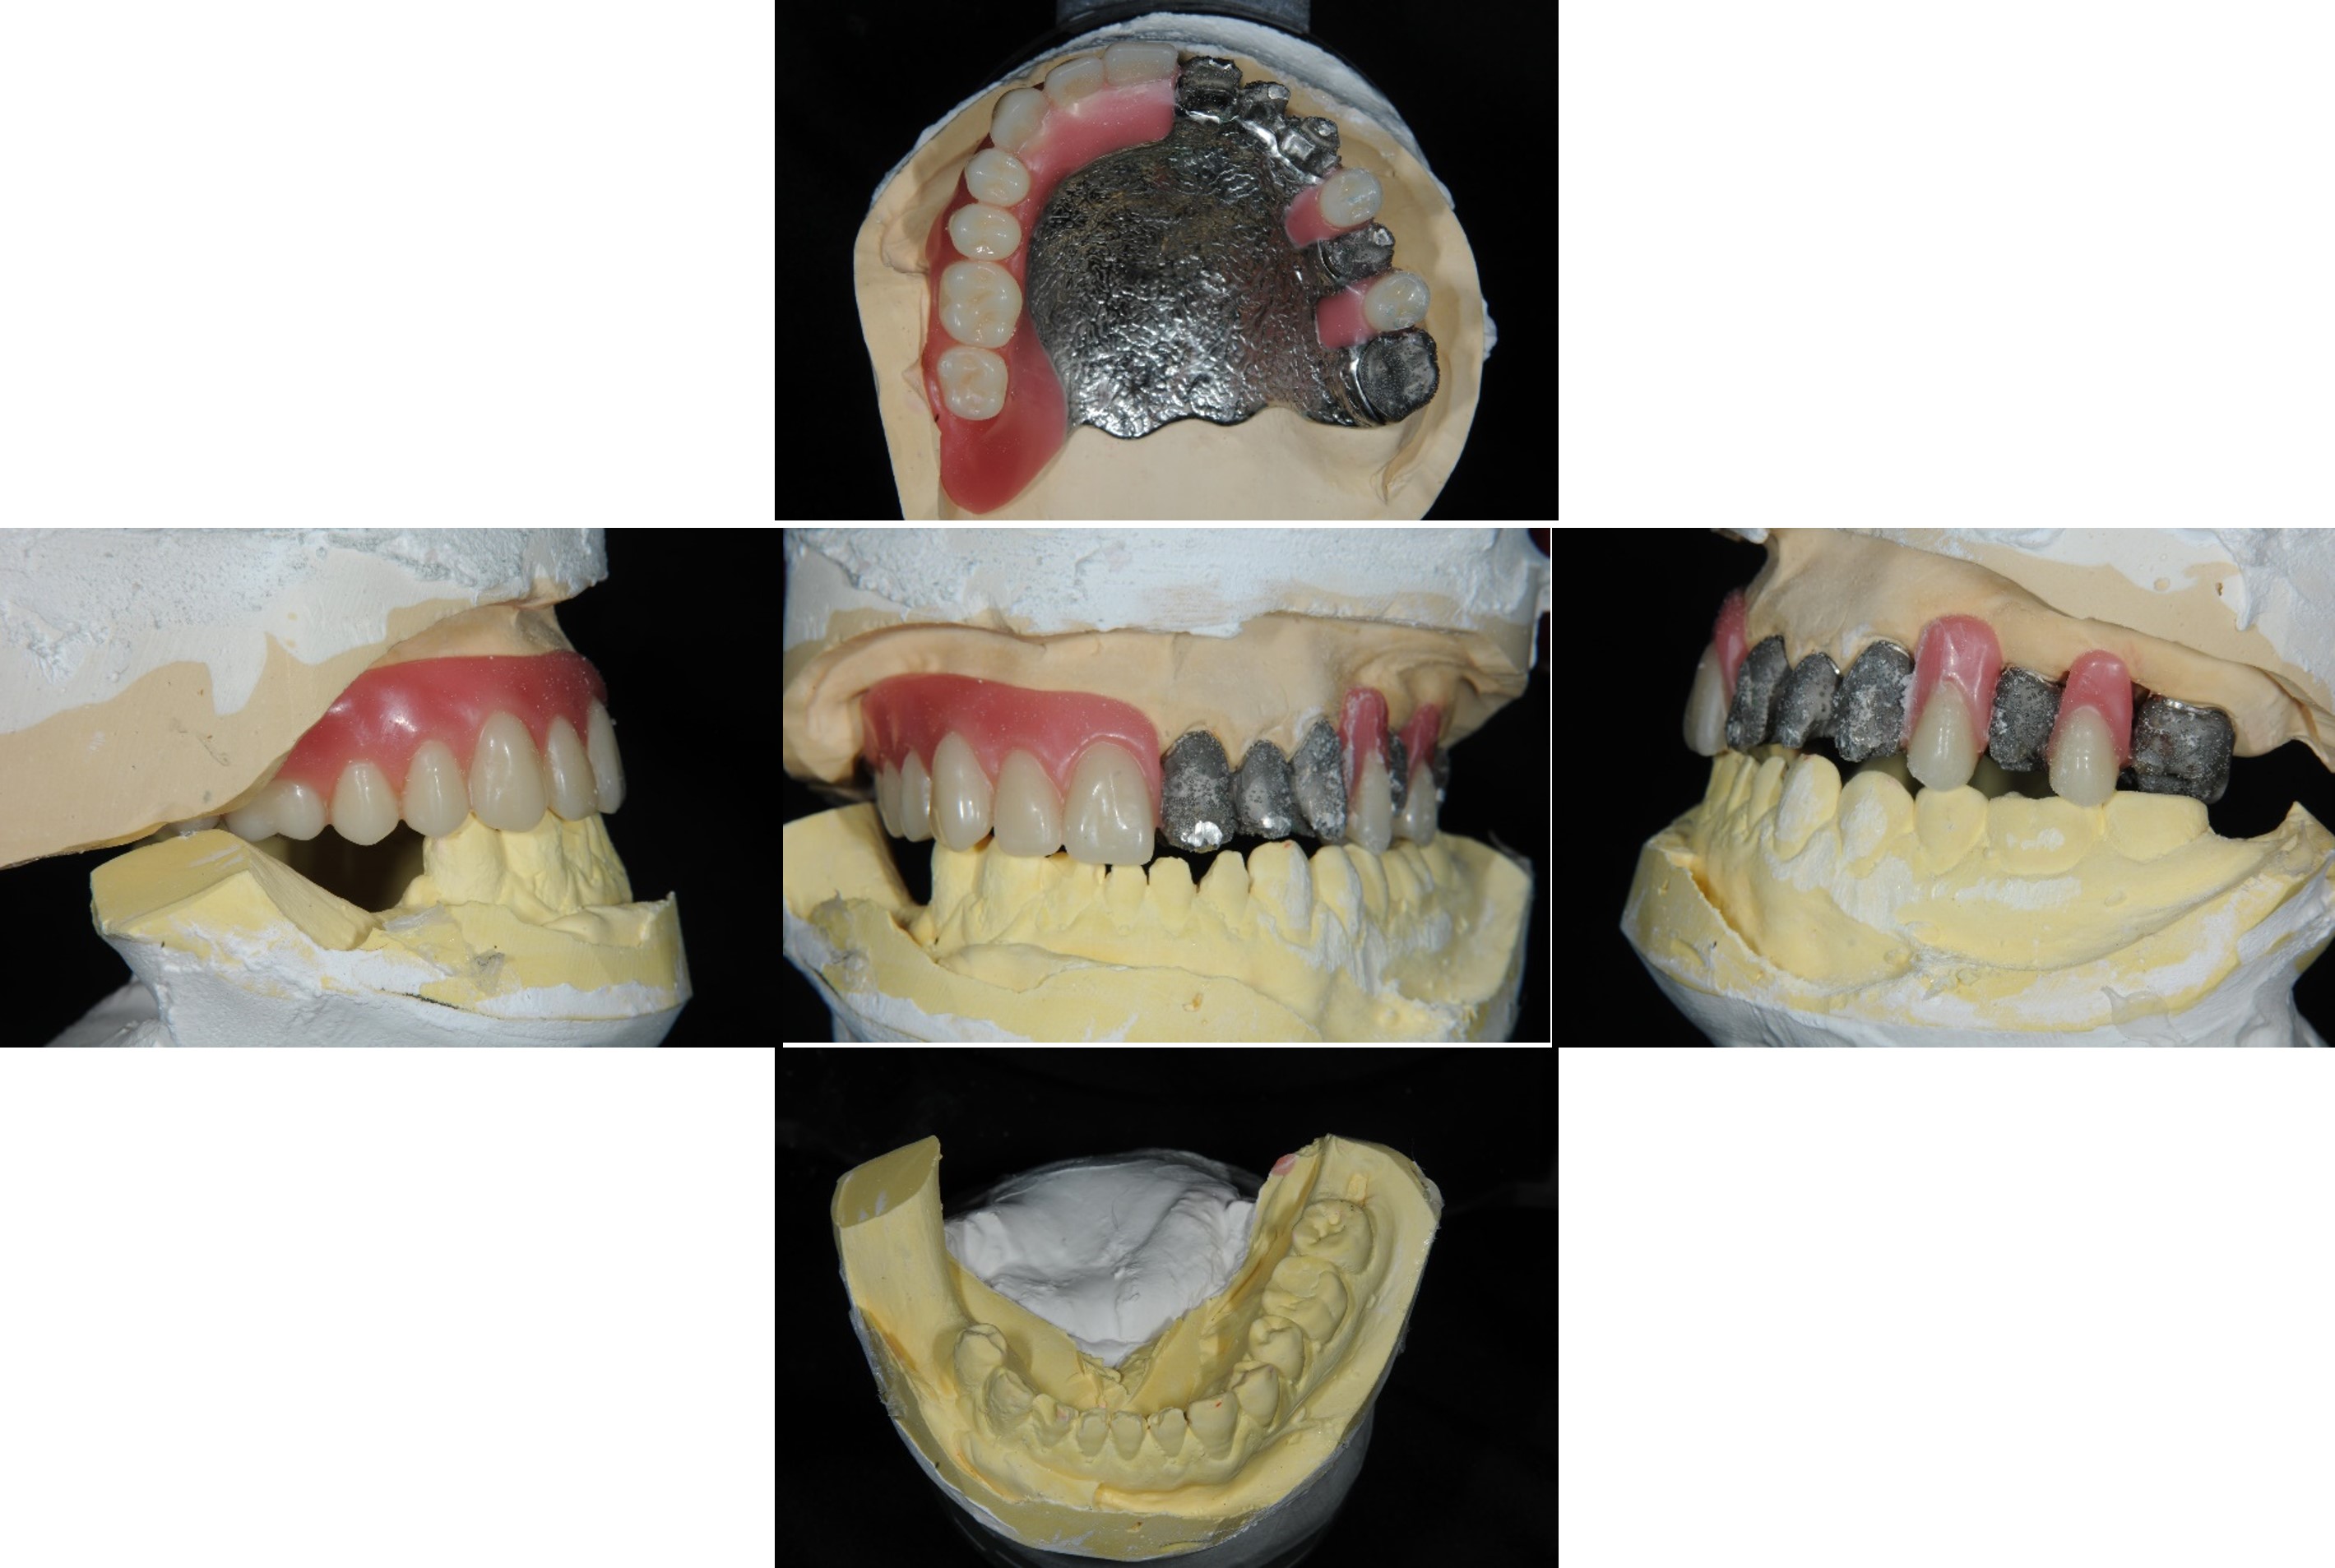

蠟牙製作

組合後外冠及活假牙套件

外冠及活動假牙套件